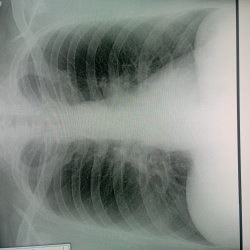

Здравствуйте! Молодой человек пришёл на комиссию, есть ли справа кальцинаты? Также интересует тень на фоне 2 межреберья слева на фоне сосудов - тоже сосуд? Второй снимок выполнен в задней проекции....